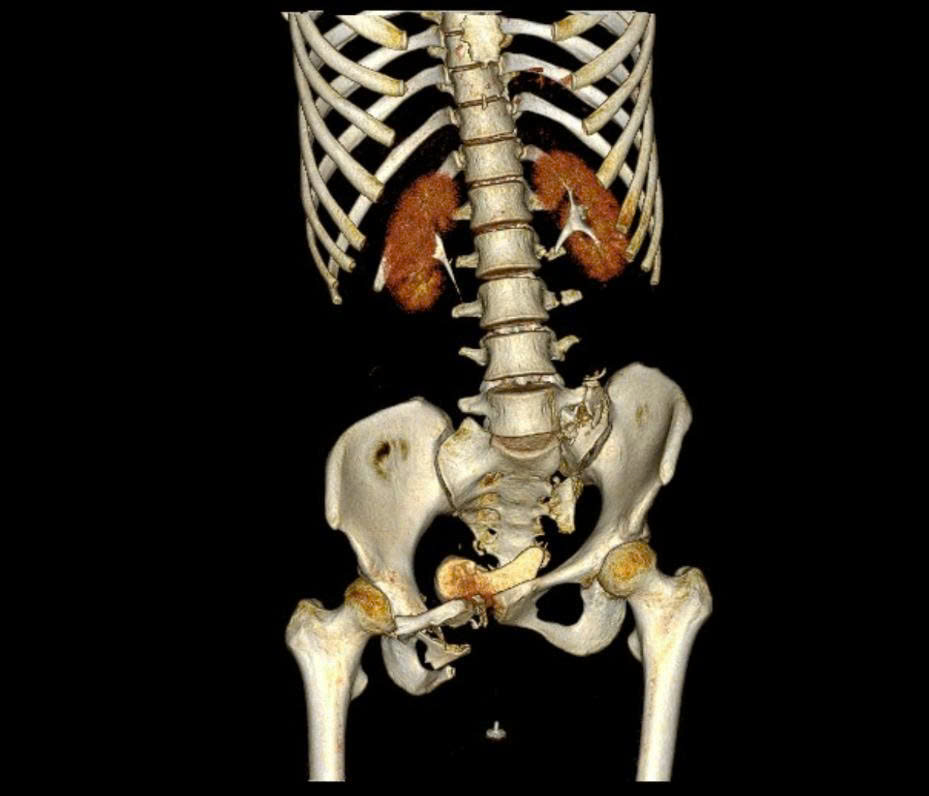

BSCKI Trần Quang Khanh, Khoa Phẫu thuật chi dưới, Viện Chấn thương Chỉnh hình, Bệnh viện Quân y 175, một trong những bác sĩ trực tiếp tham gia phẫu thuật, cho biết chị H. bị gãy khung chậu kiểu "gió thổi" - một dạng gãy rất phức tạp, chiếm khoảng 6% các trường hợp gãy khung chậu. Đây là loại gãy do chấn thương năng lượng cao, kết hợp giữa lực nén trước–sau và lực tác động bên, khiến một bên cánh chậu mở ra, bên còn lại khép lại, tạo hình ảnh đặc trưng như 'bị gió thổi'.

Hình ảnh chụp Xquang của bệnh nhân sau phẫu thuật

Thường tổn thương còn đi kèm gãy xương cùng và tổn thương khớp mu, làm mất vững toàn bộ vòng chậu, gây nguy hiểm tính mạng nếu không được xử trí đúng cách.

"Ở trường hợp này, khung chậu mất vững cả cung trước và sau nên sau khi nắn chỉnh, chúng tôi cố định cung trước bằng nẹp vít và cung sau bằng vít xốp" – BS Khanh cho hay.